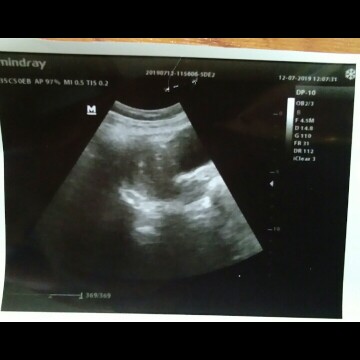

Hasil USG kehamilan pertama sy... Adakah bunda yang bisa membaca hasilnya tersebut..???

Blm ada keterangannya mak. Ini namanya penebalan dinding rahim harus bener² dijaga. Kalo mak kecapean bs keluar flek. Karena penbalan dinding rahim itu bs terjadi 2 kemungkinan. Mau haid atau mau hamil. Nah diliat lagi hasil tespack nya. Kalo tespacknya positif insyaAllah positif hamil. Jaga diri baik² Saya dl juga 6w masih penebalan dinding rahim. Suruh balik lagi 2minggu tp saya gak balik. Karena ketakutan. Akhirnya saya balik pas usia 13w. (ini hitungan hpht) Saat saya usg di usia 13w (hitungan hpht) tnyata usia janinnya masih terhitung 11w saat diusg. Jd hitungan hpht ku sm hitungan usg beda 2 minggu. Itu dikarenakan haid saya yang tidak teratur mak. Tp alhamdulillah 11w dedenya normal dan bs gerak² dan juga djj + terdengar. Temen saya 4w kanting sudah keliatan tp tnyata pas 11w janin gak berkembang 😢kasian banget dia.

Baca lagiSepertinya baru penebalan dinding Rahim aja yaa Bun.soalnya gak ad keterangannya,saya waktu USG pertama kali UK 5weeks udh terlihat kantung kehamilannya,skrg UK saya 12weeks,kl usia kehamilan baru beberapa Minggu kemungkinan hanya penebalan dinding rahim bun.jgn capek" yaa bun.jaga pola makannya mulai dr skrg.

Selain penebalan dinding rahim sy jg liat ada bulatan kecil yg kemungkinan kantong kehamilan. Tp dokter blm ngasih tanda GS.x jd kayaknya harus balik lg 2minggu untuk memastikan kehamilannya bunda. Paling usianya masih dibawah 5minggu makanya dokter gk ngasih keterangan apa2 di hasil usgnya

Usia nya kandungan bunda brapa... Kog di keterangan gak jelas ya bun... Biasanya di tengah di perlihatkan klw hamil ada kantong hamil n janin nya... Klw masih muda blm kelihatan kayak nya bun

Kayanya hamil bunda masih muda ya bun? Soalnya blm keliatan kantungnya, itu kayanya baru penebalan rahim aja

Klo nggk ada keterangan gitu biasanya baru ad kantong rahimnya aja. Sma kyk pnya saya kmrn baru 4 week